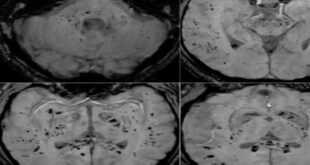

تحليل بالرنين المغناطيسي يكشف تأثير كوفيد-19 المستمر على الدماغ

أظهر تحليل صور بالرنين المغناطيسي أن فيروس كوفيد-19 يترك أثرا لا يُمحى في الدماغ، ويستمر تأثيره حتى بعد التعافي التام. أظهرت دراسة حديثة أجراها علماء في جامعة غريفيث الأسترالية ونُشرت في مجلة Brain, Behavior, & Immunity Health أن فيروس كوفيد-19 لا يؤثر على الجهاز التنفسي فحسب، بل يترك أثرا ملموسا …